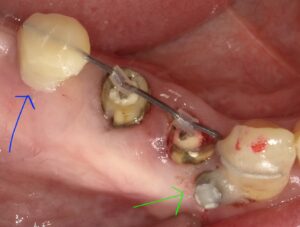

画像の緑と青がアンカースクリューです。

真ん中の2本の歯が虫歯で歯茎より下にしか

歯が残っていません。

そのため鉄棒のように両隣の歯に針金を乗せて

歯の方にはフックをつけてゴムで引っ張り上げています。

しかしこの場合は奥の方に歯がありませんのでアンカースクリューを

埋め込んで樹脂で歯を作っています。